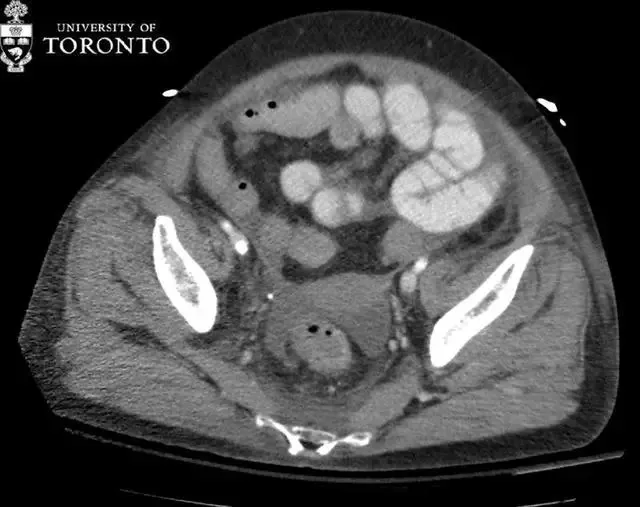

【治疗|精选病例:典型的急性坏死性胰腺炎】治疗:患者静脉用抗生素治疗了两个星期 , 之后患者出现了大量的混合性腹水 , 胰床上见 aeric 脓肿 , 位于钩突下方右侧可见另一个腹膜后脓肿(黄色箭头) 。

两处脓肿分别在超声引导(右)和 CT 引导(左)下行经皮穿刺引流术 。 16-Fr 多功能引流导管放置在脓肿中 , 吸出带碎屑的脓液 。 在随访的 CT 引导下引流中 , 排水管处于较好的位置(粉红色箭头) , 脓肿的大小也减少 , 但不幸的是 , 病人在出现肠系膜缺血不久后死亡 。

胰腺脓肿可使坏死或非坏死性胰腺炎变的更复杂 , 通常在出现症状四周后才确诊 。 治疗方法是经皮或手术引流 。 在 CT 上 , 表现为包裹性积液 , 周围可见强化;内可能含有气泡(20%) 。 感染性假性囊肿需要与其相鉴别 , 它出现较晚 , 且往往与非感染假性囊肿具有相同的表现 。